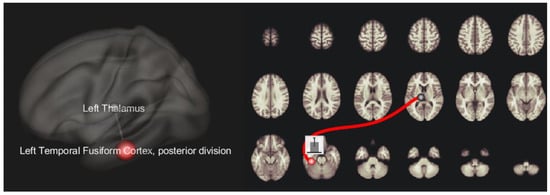

| Depressed patients > HC | |||

| Left thalamus | Left posterior-temporal fusiform cortex | 4.2 | 0.01 |

| Depressed FTD > HC | |||

| Left thalamus | Left posterior-temporal fusiform cortex | 3.6 | 0.05 |

| Depressed PD > HC | |||

| Left thalamus | Left posterior-temporal fusiform cortex | 3.6 | 0.04 |